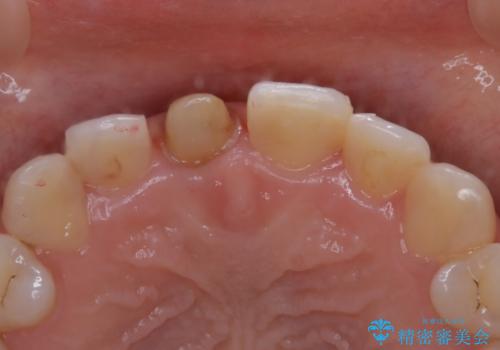

- 前歯一本だけ色が暗いことが気になりご相談にいらした患者様です。周辺の歯と色味をぴったり合わせることで自然な仕上がりになりました。

根管治療をした歯は神経のある歯と比較して強度が下がり、長期的に破折のリスクが高まると言われています。破折のリスクを軽減させるため、根管治療を行った歯に対しては歯冠をすべて覆うクラウンという被せ物にて補綴処置を行います。

適合不良の補綴物は二次的な虫歯発生のリスクが高まります。

自費診療で用いられる材料は保険適応の材料に比べて、より精密で適合の良い被せ物作ることができるため、長期的な虫歯のリスクを大幅に減らすことが可能です。